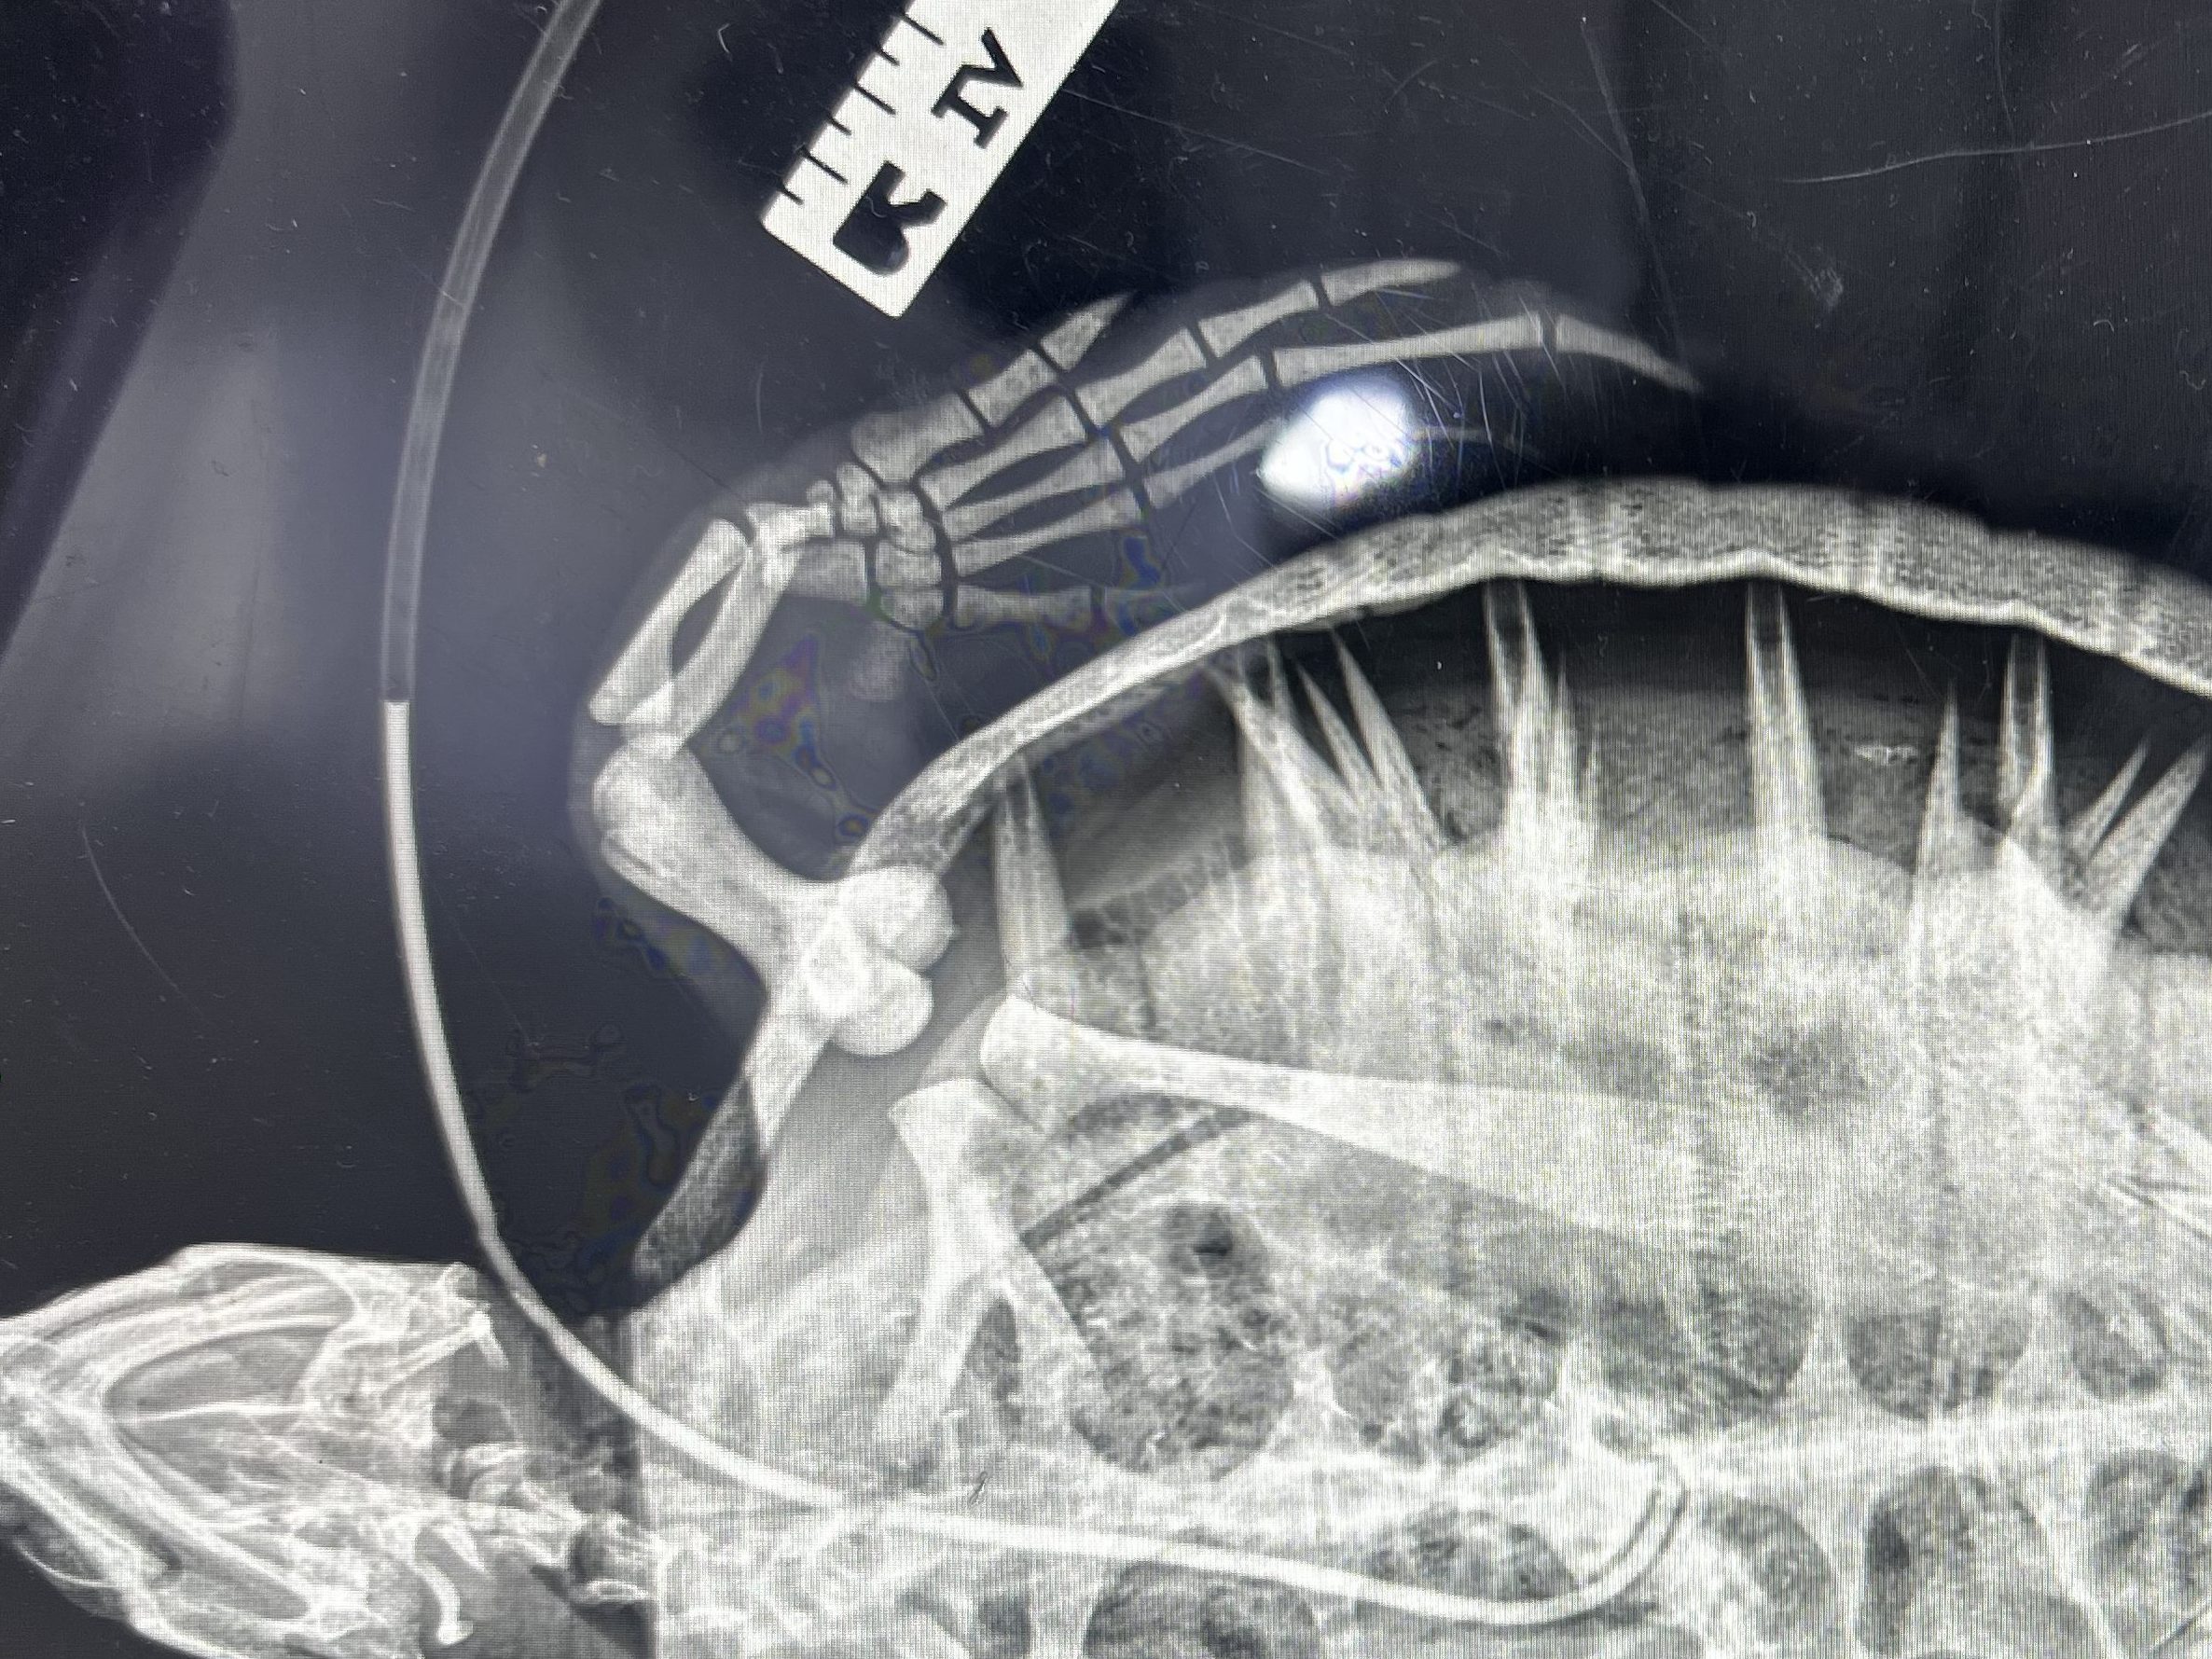

Proper dental assessments require radiographs, as pictured above, and for the patient to be sedated (especially when it’s a lion). A majority of the animals are trained to voluntarily receive the sedation via injection and are then transported up to the hospital with the help of the veterinary, keeper, and trained animal response teams.